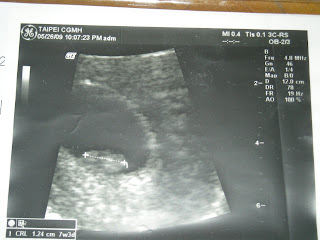

7W3D

一週後也就是5/26我又回到醫院.

由於我的大姨媽不規則,

不記得最後一次什麼時候,

只能從目前胎兒大小去推算出預產期.

超音波檢查結果胎兒是1.24CM, 懷孕7W3D,

預產期是2009/1/11.